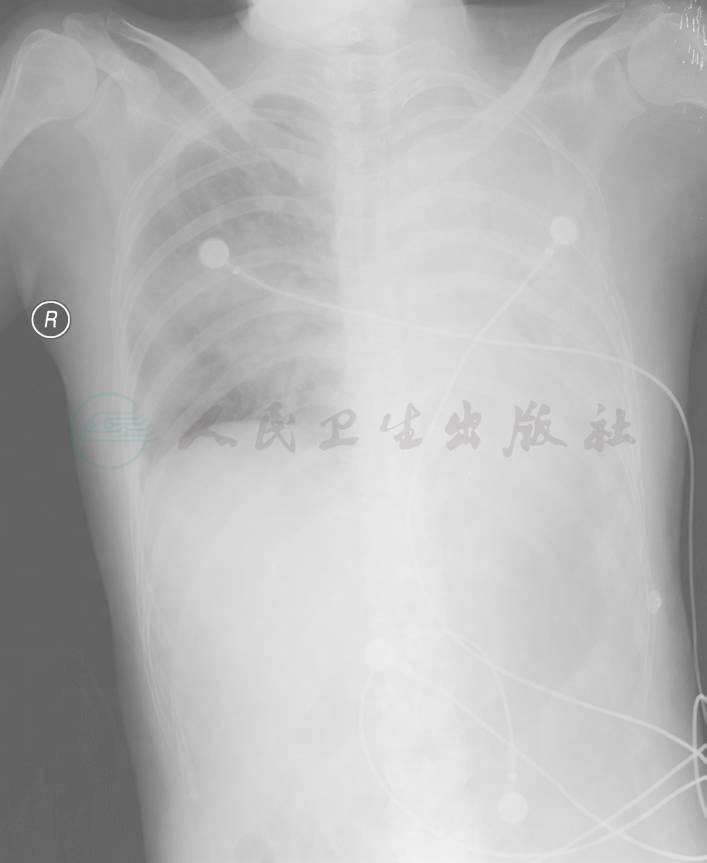

白细胞13.04×109/L,中性粒细胞比率 70.6%,中性粒细胞数为9.9×109/L,血红蛋白78g/L。尿常规正常。血糖、肝肾功能、电解质正常。血细胞沉降率41mm/h,C反应蛋白25mg/L,类风湿因子16.2 IU/ml,白蛋白15g/L。动脉血气(吸氧 3L/min):pH 7.496,PaCO2 29.77mmHg,PaO2 73.16mmHg,HCO3- 22.7mmol/L。肥达反应、外斐反应阴性。HIV抗体阴性。胸片(2月15日):①右肺感染;②左肺感染并含气不全;③左侧少量胸腔积液(图1)。

图 1 右肺野可见多发团片状模糊影,左肺野呈均匀致密影,左心缘及左膈面消失